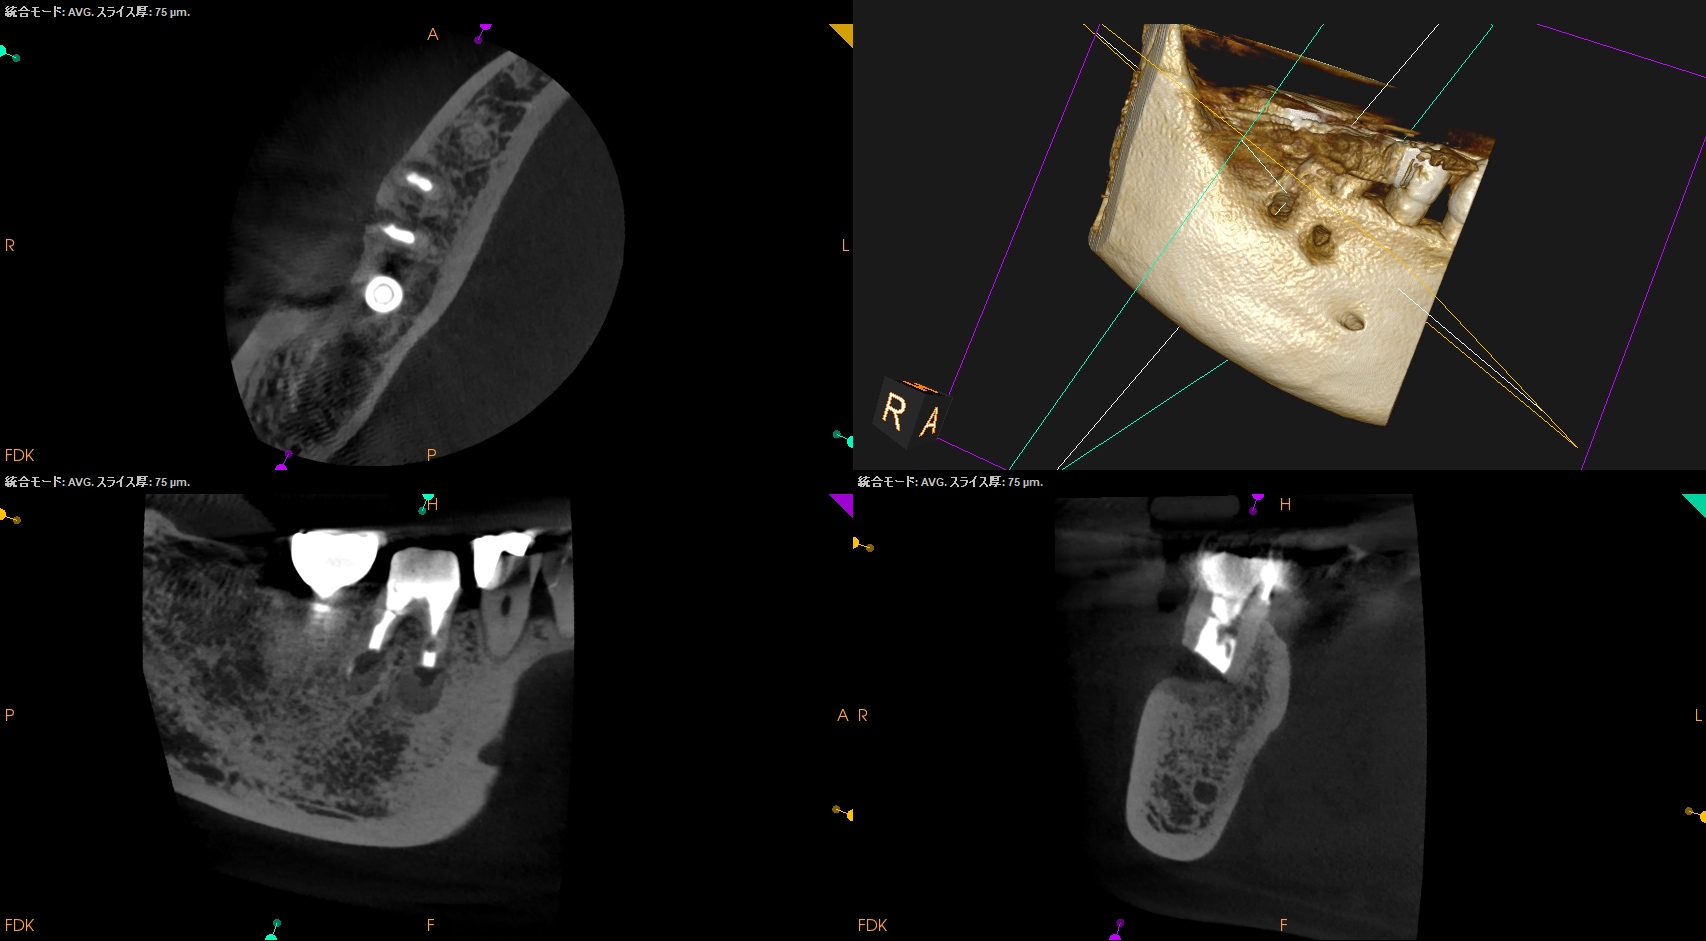

Apicoectomy時にはApexの位置を正確に把握する必要がある臨床的理由〜#30 Crown, Post Core removal⇨M,D Apicoectomy 1回法

治療から5ヶ月が経過していた。

#30 M,D Apicoectomy 5M recall(2026.3.30)

B

外科直後と比較した。

最終補綴もOKだ。